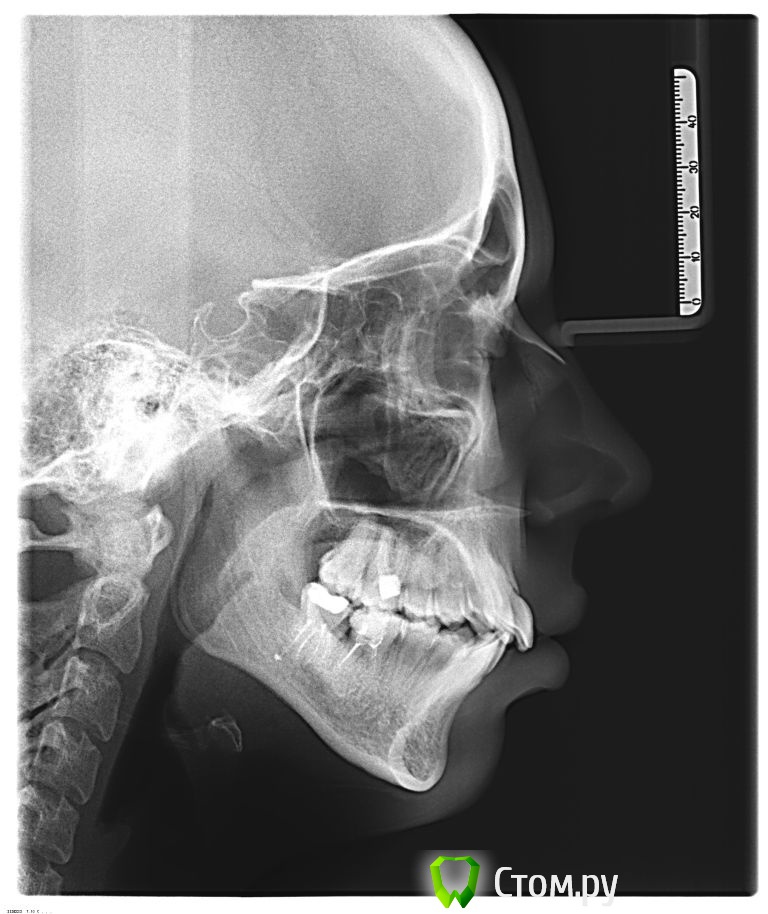

89kristy Опубликовано 15 июня, 2014 Поделиться Опубликовано 15 июня, 2014 Здравствуйте, помогите советом. Ортодонт советует удалять 4 премоляра но из-за верхней микрогнатии боюсь что верхняя губа будет западать. Возможно ли решение моей проблемы с помощью остеопластики или она даст только косметический эффект и удаления премоляров не избежать? ÐSNA -88° - антепозиция ВЧ (82±3,5)ÐSNB -81 - N (80±3,5)ÐANB -7° - дист.оклюзияÐF -88° - лицевой профиль выпуклыйÐI -84° - N (85±5)ÐH -87° - задняя ротация НЧÐGo -125° - NÐBs -30° - (N-28) – вертикальный тип ростаÐT -20° - (N-10) – челюстный профиль выпуклыйSnaSnp = 45 (N=46,9) –верхняя микрогнатияNse=67GoPg=70 – нормогнатияВерх Ð59° (57,5±7)- NНиз Ð103° (95±7) Ссылка на комментарий

Skip Опубликовано 16 июня, 2014 Поделиться Опубликовано 16 июня, 2014 Нет там никакой "верхней микрогнатии". А вот нижняя челюсть, действительно, немного укорочена. Удалив верхние премоляры, Вам сделают верхнюю челюсть короткой, учитывая что сейчас она нормального размера. Исходя из этого, считаю преступлением, укорачивать верхнюю челюсть, подстраивая её под короткую нижнюю. 3 Ссылка на комментарий

Force Опубликовано 18 июня, 2014 Поделиться Опубликовано 18 июня, 2014 Прямо противоположный. Оставить в покое верхнюю и думать о нижней. Разные ортодонты по разному это делают. Ссылка на комментарий